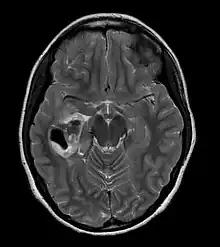

| CT scan of a brain with pleomorphic xanthoastrocytoma. The classic radiographic appearance is one of a superficially situated tumor, here a mural nodule, associated with an underlying cyst. |

Pleomorphic xanthoastrocytoma usually develops within the supratentorial region (the area of the brain located above the tentorium cerebelli). It is generally located superficially (in the uppermost sections) in the cerebral hemispheres and involves the leptomeninges. It rarely arises from the spinal cord.

These tumors are formed through the mitosis of astrocytes. They are found in the area of the temples, in the brain's frontal lobe or on top of the parietal lobe. In about 20% of cases, tumors exist in more than one lobe.